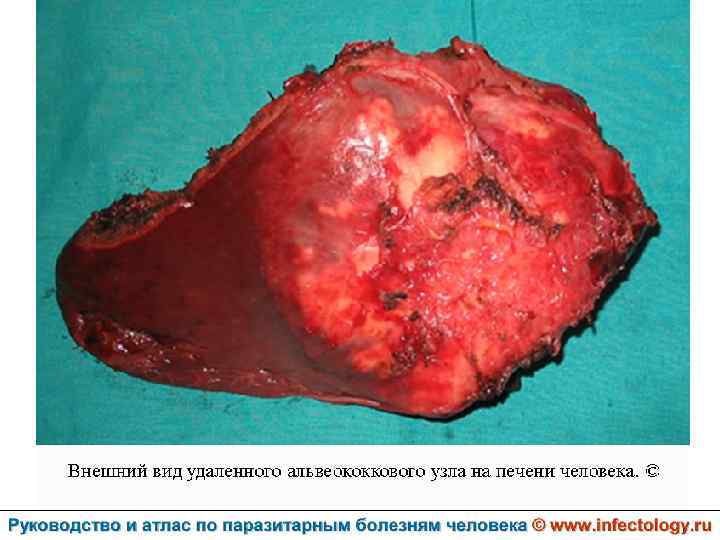

Альвеолярный (многокамерный) эхинококкоз человека (альвеолярный гидатидоз) (шифр по МКБ 10 - B 67. 5 -7) – зоонозный биогельминтоз, характеризующийся чрезвычайно тяжелым хроническим течением, первичным опухолевидным поражением печени, нередко с метастазами в головной мозг и легкие, а также во многие другие органы. Заболевание часто заканчивается летально.